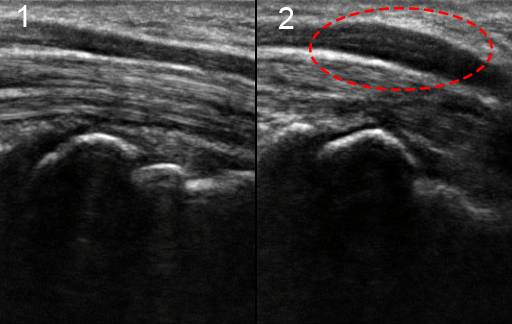

Wrist Carpal Tunnel Syndrome with Nerve Swelling Image

Normal

Swelling